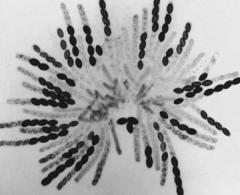

Take a look—a careful look—and figure out what you are seeing. I am delighted to once again present a winning image from the Science and Engineering Visualization Challenge, sponsored by the journal Science and the U. S. National Science Foundation, where for the fourth year I am privileged to be a judge. The moment this image came on the screen, we all sighed with wonder. We're seeing the head region of a 2,000-year-old mummy of an Egyptian child (notice the head within the cartonnage?) from the Rosicrucian Egyptian Museum in San Jose, California. The detail is part of a larger three-dimensional image reconstructed from 60,000 exceptionally high-resolution two-dimensional scans, made without disturbing the fragile mummy-case. The team was led by endodontist W. Paul Brown of the Stanford-NASA National Biocomputation Center, working with physicist Rebecca Fahrig in the Department of Radiology and other colleagues at the Stanford University School of Medicine.

W. P. B. A team of physicists and radiologists at Stanford used a Siemens AXIOM C-arm CT scanner to generate 2-D slices about 200 microns thick, considerably thinner than the 750-micron slices used to create the 3-D visualization of King Tut's mummy. Robert Cheng, Eric Herbranson, Christof Reinhart, Juel Herbranson, Kevin Montgomery, Afshad Mistri and Amy Ladd used Volume Graphics' real-time ray-tracing technology to render and visualize the data set on a Silicon Graphics Prism workstation for the creation of the 3-D models.

W. P. B. From a series of detailed studies, we arrived at the following conclusions: The mummy was a female, between the ages of four and five years old, who probably died from a common intestinal illness or other disease, since we found no signs of injury (half of all Egyptian children died before their fifth year). Her family was probably wealthy—a scented resin was applied on the golden face mask.

W. P. B. Yes, we colored the image based on tissue density, thus making the teeth white (high calcium/highest density) and the bones a light sort of bone color, and finally applying reddish tints to the soft tissue.